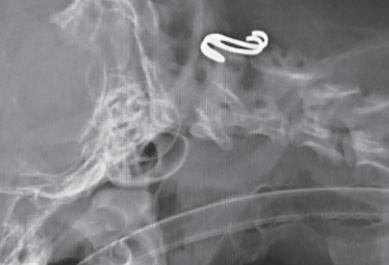

Tratamiento quirúrgico de la subluxación atlantoaxial 30

• Tratamiento quirúrgico de la subluxación atlantoaxial